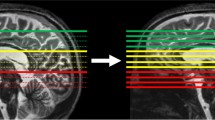

Single-shot T2-weighted images such as HASTE or SSFSE are used in sagittal, coronal, and axial planes for clinical evaluation of the fetal brain. Due to motion degradation of slices, these acquisitions are often not exactly in the desired plane and often not exactly orthogonal. Many groups have developed post-processing approaches to combine the three planes together to create a coherent higher resolution 3D brain volume (Fig. 9) [27–30], but these methods currently require manual intervention and many hours of computational time. In addition most tools fail approximately 50 % of the time due to poor image quality as a result of motion or image artifacts. As a result such much needed tools for clinical fetal imaging are not yet available.